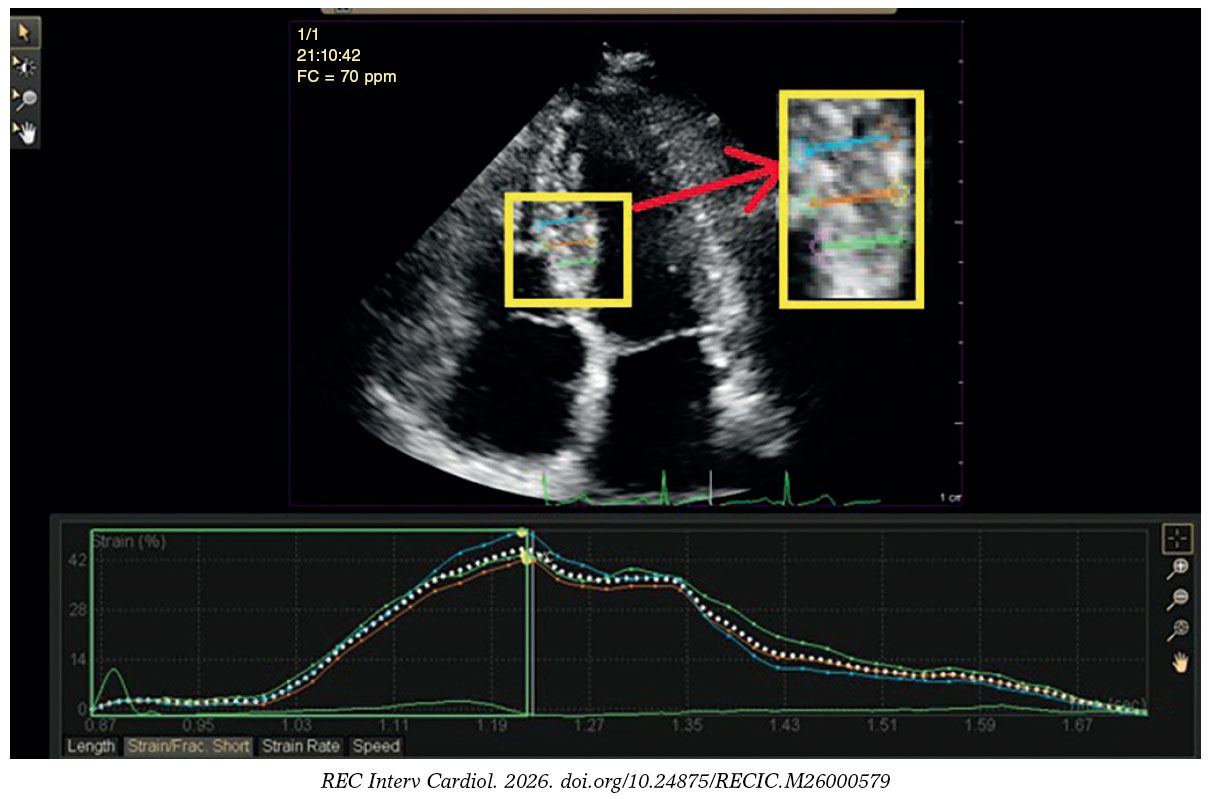

Figura 2. Análisis de deformación radial regional de un participante del estudio con cardiopatía isquémica estable que muestra un 42% de deformación en el segmento inferoseptal medio.